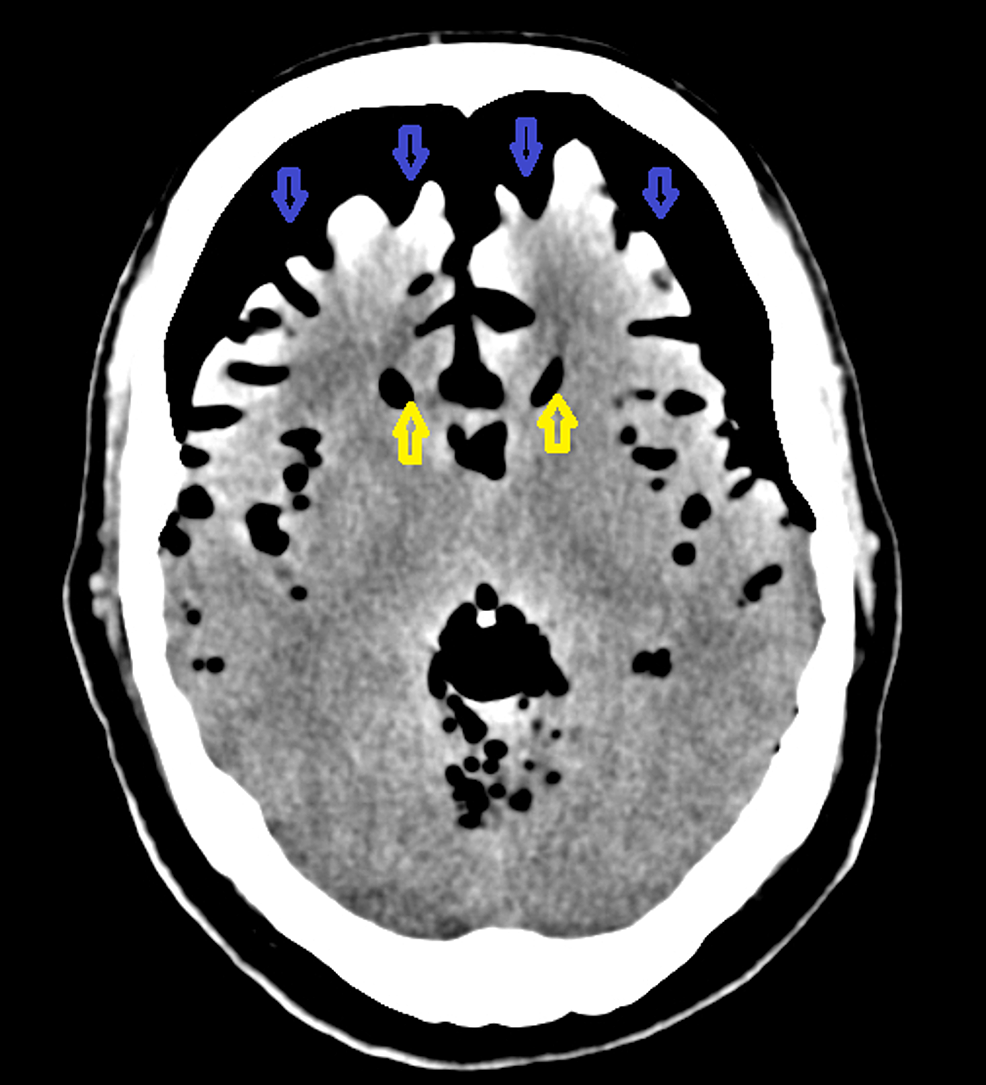

Mount Fuji Sign Ct

Mount Fuji Sign Tension Pneumocephalus Axial Non Contrast Brain Ct Download Scientific Diagram

Mount Fuji Sign Due To Tension Pneumocephalus Is Observed In Axial Ct Download Scientific Diagram